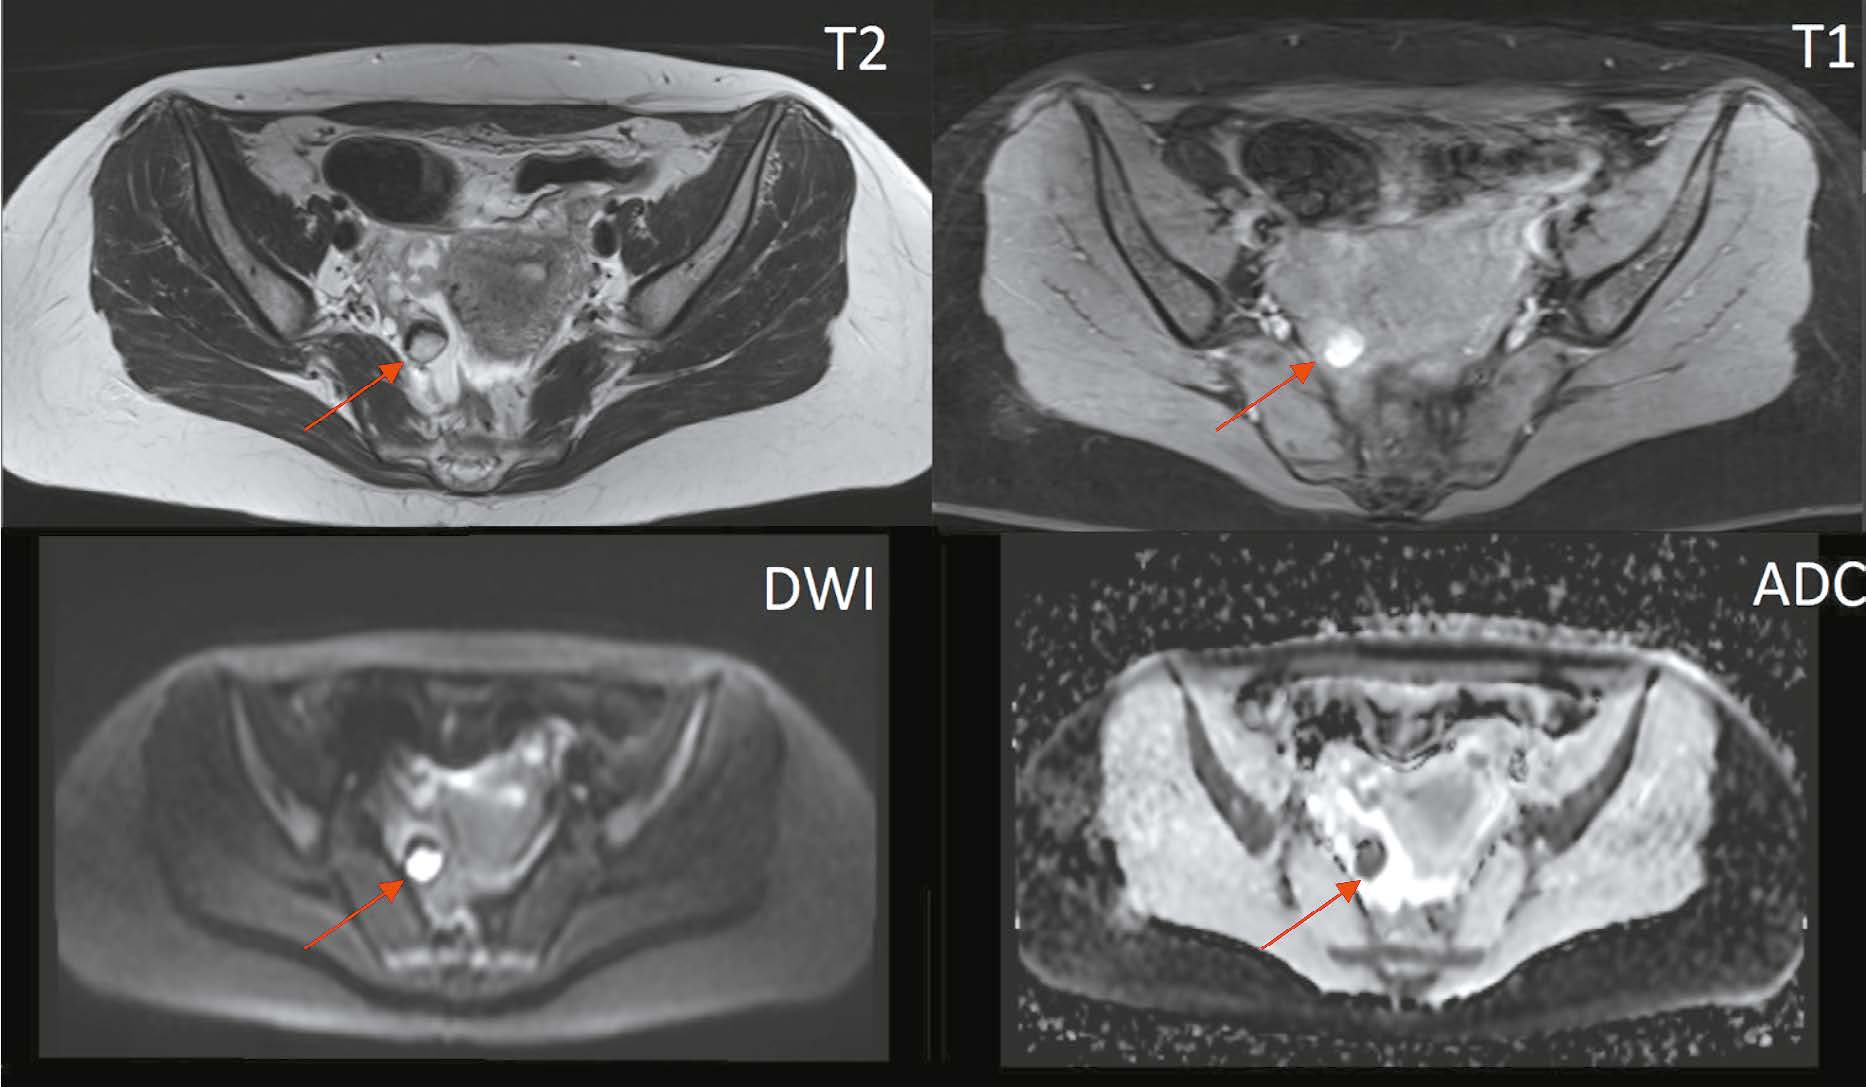

Магнитно-резонансная томография в диагностике серозной аденокарциномы фаллопиевых труб: клинический случай

Серозная аденокарцинома фаллопиевых труб — крайне редкая и сложная для диагностики форма злокачественных новообразований женской репродуктивной системы. Данная патология часто протекает бессимптомно или сопровождается неспецифической клинической картиной, включающей серозно-кровянистые выделения из влагалища, коликообразную боль в нижней части живота и таза. Эти симптомы известны в литературе как триада Лацко и считаются патогномоничными для рака маточной трубы, однако их сочетание наблюдается менее чем у 15% больных. Низкая частота встречаемости и отсутствие патогномоничной клинической картины приводят к высокому числу диагностических ошибок либо к выявлению заболевания уже в запущенной стадии, что существенно ухудшает прогноз для пациента. Точный диагноз на предоперационном этапе устанавливается всего лишь в 4% случаев. В данном клиническом наблюдении приводится описание случая серозной аденокарциномы фаллопиевых труб со всеми проявлениями триады Лацко и МР-картины, позволившей заподозрить наличие у пациентки серозной аденокарциномы фаллопиевых труб на предоперационном этапе.